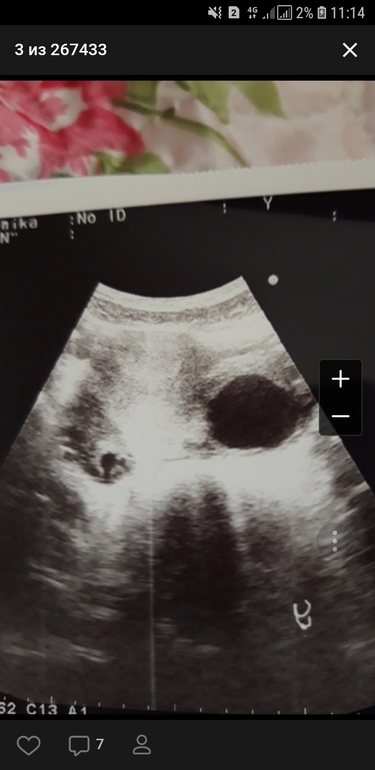

Это фото яичника. Большое черное пятно это киста, вокруг несколько маленьких фолликулов

прежде чем "что-то видеть" посмотрите хотя бы как выглядит беременность малого срока на узи. Киста у вас шикарная. И хорошо что еще маленькая, у меня была 10 сантиметров, я пила с 10 по 25ый дц дюфастон, за 1 такой прогон киста сдулась.

Киста фолликулярная левогояичника 36мм, плодное яйцо не лоцируется, то есть не видит